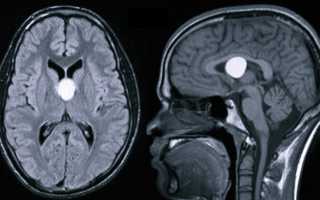

Киста головного мозга — объемное внутричерепное образование, представляющее собой наполненную жидкостью полость. Часто имеет скрытое субклиническое течение без увеличения размеров. Проявляется в основном симптомами внутричерепной гипертензии и эпилептическими пароксизмами. Возможна очаговая симптоматика, соответствующая расположению кисты. Диагностируется по результатам МРТ и КТ мозга, у детей грудного возраста — по данным нейросонографии. Лечение проводится при прогрессирующем росте кисты и развитии осложнений, состоит в хирургическом удалении или аспирации кисты.

Использование УЗИ позволяет выявить некоторые врожденные кисты еще в период внутриутробного развития, после рождения ребенка и до закрытия его большого родничка диагностика возможна при помощи нейросонографии. В дальнейшем визуализировать кисту можно посредством КТ или МРТ головного мозга. Для дифференцировки кистозного образования от опухоли мозга эти исследования проводят с контрастированием, поскольку в отличие от опухоли, киста не накапливает в себе контрастное вещество. Для лучшей визуализации кистозной полости возможно введение в нее контраста путем пункции кисты. В отличие от МРТ, КТ головного мозга дает возможность судить о вязкости содержимого кисты по плотности ее изображения, что учитывается при планировании хирургического лечения. Основополагающее значение имеет не только установление диагноза, но и непрерывное наблюдение за кистозным образованием для оценки изменения его объема в динамике. При постинсультном генезе кисты дополнительно прибегают к сосудистым обследованиям: дуплексному сканированию, УЗДГ, КТ или МРТ сосудов головного мозга.

На сегодняшний день основными методами диагностики и последующего прогноза данной болезни являются МРТ (магнитно-резонансная томография) и КТ. Полученная томограмма показывает состояние всех составляющих мозга (эпифиза, мозжечка, гипофиза, нервных ганглий и других частей). С ее помощью можно увидеть место расположения перивентрикулярного глиозного очага и атрофических рубцовых следов внутри головного мозга без вскрытия черепной коробки, оценить их форму, размеры и интраселлярный рост.

Кроме того, данные способы обследования позволяют сделать дифференциальную диагностику промежуточного состояния между доброкачественной кистой и злокачественной опухолью. После внутривенного введения специального контрастного вещества его продукт накапливается в опухолевых тканях, а киста при этом не становится контрастной.